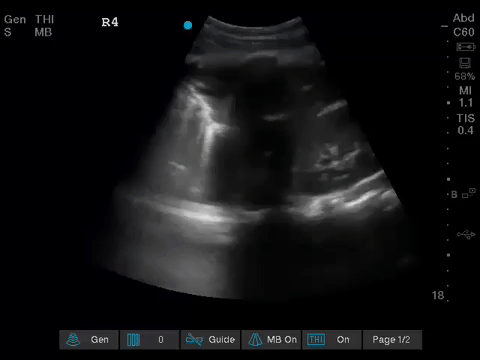

The POCUS team was asked to specifically to assess her lungs to help determine the cause of her dramatically increased oxygen requirements.

Before giving their clinical interpretation of the LUS findings, the POCUS team also scanned the heart and vasculature to obtain a more complete picture.

1. When scanning the lungs, a comprehensive, bilateral lung scan is far superior to a single clip; as this will offer more information and permit an interpretation based on the overall pattern of findings. Had this patient only had the R1 area scanned, for example, we may have reached the erroneous conclusion that her hypoxemia was likely due to pulmonary edema.

2. When scanning critically ill patients, it is almost always indicated to scan the heart, lungs, and vasculature together (as opposed to scanning a single system). You never know what you might find!